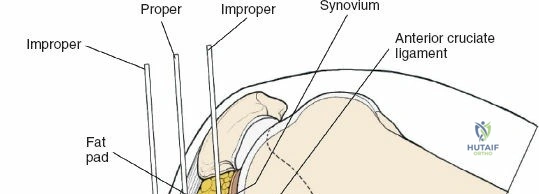

- Proximal Tibia: The preferred entry point for tibial nails lies in the proximal tibia, typically between the anterior tibial spine and the lateral edge of the patellar tendon. The infrapatellar fat pad (Hoffa's fat pad) must be navigated. Careful attention to the articular surface is paramount to avoid iatrogenic damage to the tibial plateau. The patellar tendon can be split or approached paratendinously, with long-term studies showing no significant difference in knee pain.

The incision should be adequate to allow clear access to the entry point and accommodate the targeting jig. The patellar tendon can be carefully split longitudinally or approached paramedially (medial or lateral to the tendon). - Entry Point Determination: The ideal entry point is crucial for proper nail alignment and preventing iatrogenic damage. It is typically located on the anterior cortex of the tibia, just medial to the lateral edge of the patellar tendon, distal to the articular surface of the tibial plateau.

- Fluoroscopic Guidance: Use an Awl or K-wire under AP and lateral fluoroscopy to confirm the entry point. The AP view should show the wire positioned to align with the central axis of the medullary canal. The lateral view should show the wire in line with the anterior cortex, avoiding a posterior entry which can damage the posterior cortex and lead to malalignment.

- Patellar Tendon Protection: Ensure the entry reamer or awl does not scrape the posterior aspect of the patella or damage the articular cartilage.